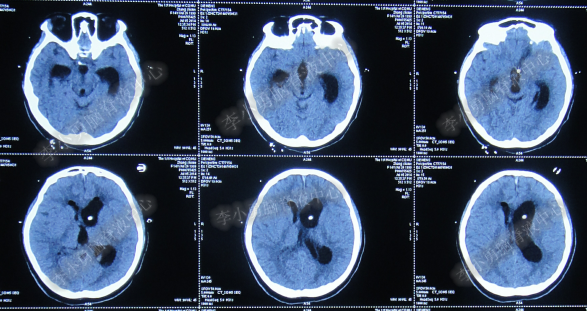

患者因恶心、呕吐伴头痛头晕,自行服药后无法自行缓解,于2014年5月29日就诊位于重庆的著名的三甲肿瘤医院,查全脑CTA和CT后诊断为“小脑蚓部占位伴幕上脑积水”(图-1、图-2)。

图-1:2014年5月29日全脑CTA

图-2:2014年5月29日头部CT